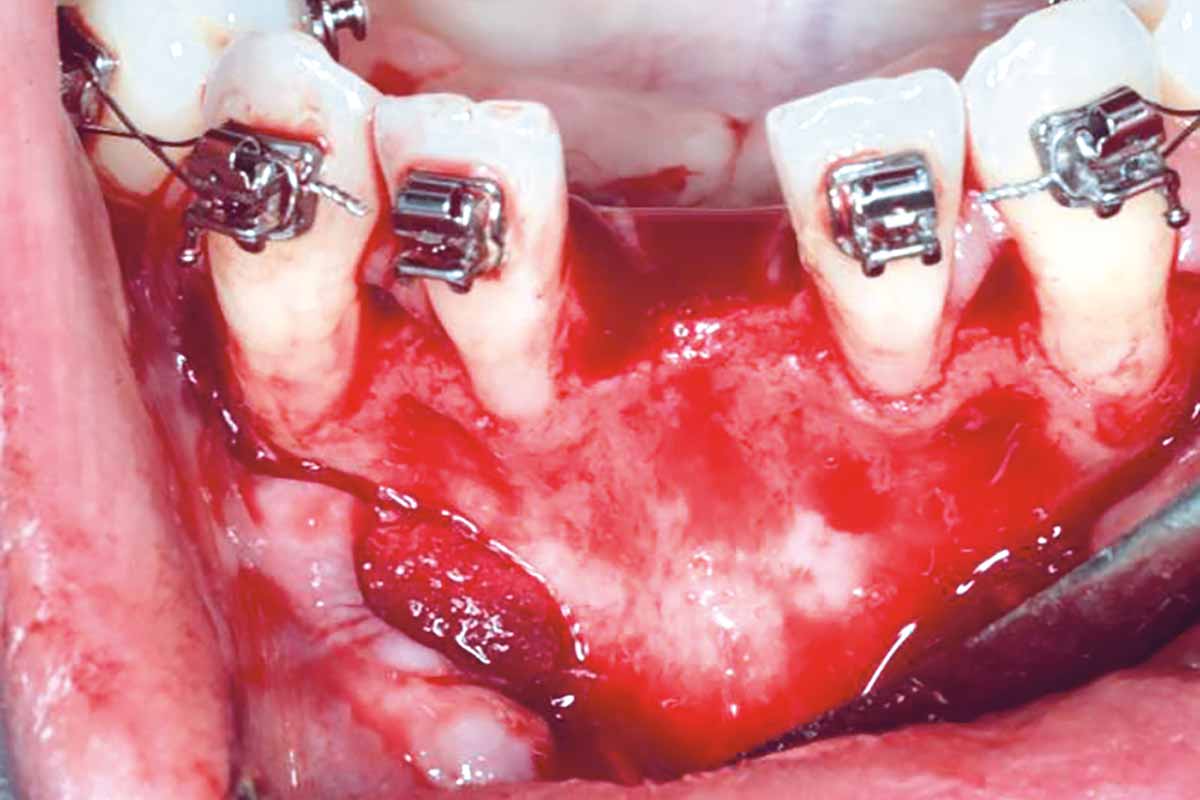

Regenerative corticotomy to compensate lower incisor malocclusion with cerabone® and mucoderm®

Initial view of the clinical case: Class III malocclusion

Treatment plan: Regenerative corticotomy (PAOO)